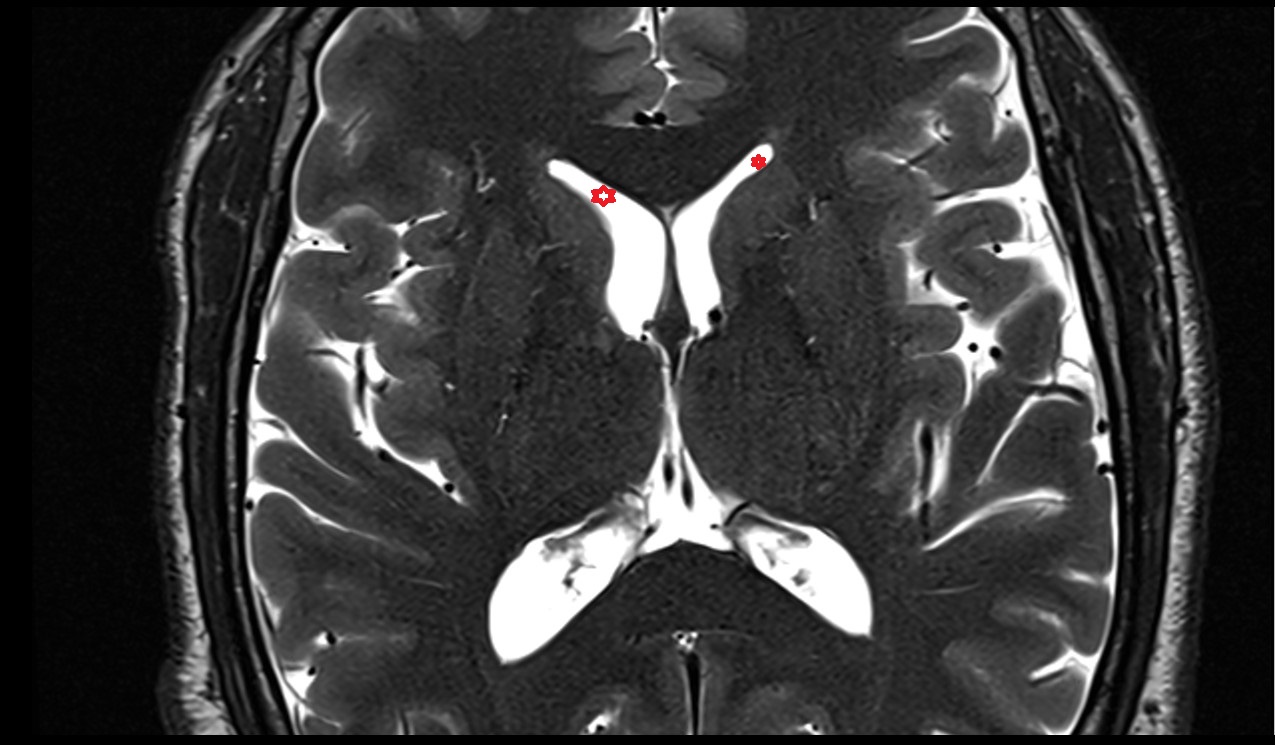

- Atrium of lateral ventricle

- Central part of lateral ventricle

- Occipital horn of lateral ventricle

- Temporal horn of lateral ventricle

- Third ventricle